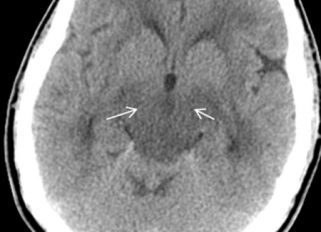

• Магнитно-резонансную томографию (МРТ);

• Компьютерную томографию (КТ).